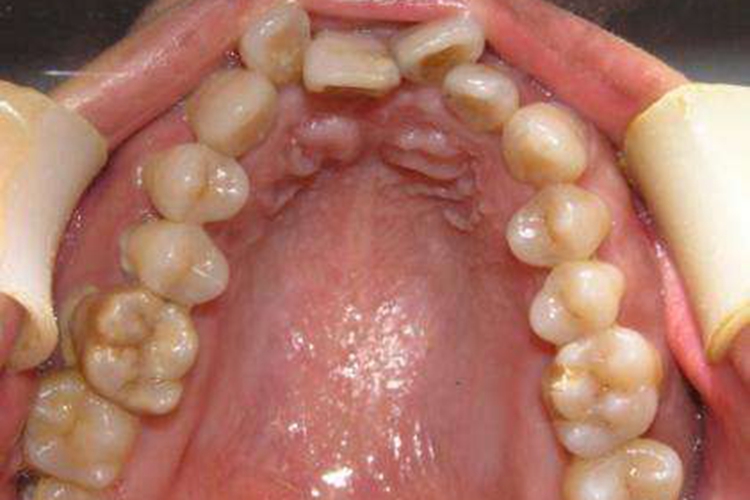

牙弓狭窄者是错(牙合)畸形的表现之一,好发于上颌牙弓,多呈现牙弓宽度不协调,两侧相对应的磨牙间距离缩短,常伴有腭盖高拱,上前牙拥挤、前突、开(牙合)畸形,上颌前突、下颌后缩,开唇漏齿等表现。